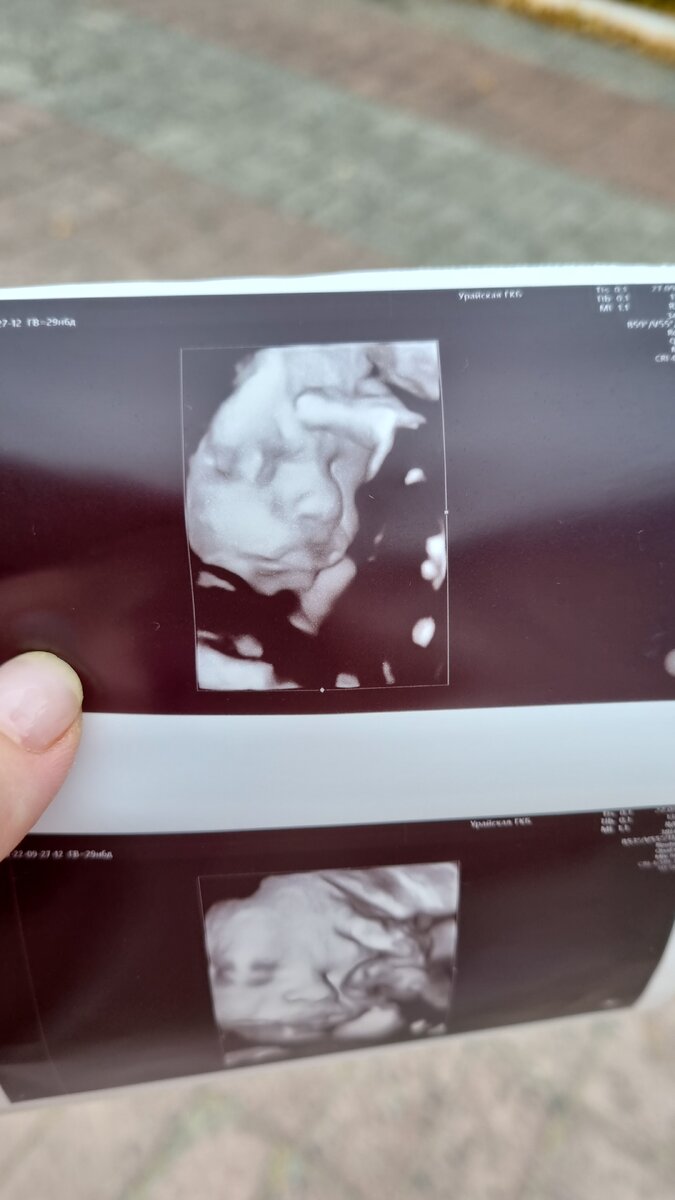

Но зато покажу фотографию с УЗИ в 30 недель последнего четвертого сыночка Прохора и его снимок сразу после рождения, а вы сами сравните, похож ли внутриутробный снимок на уже рожденного человека.

Это Прохор в 30 недель беременности. А ниже фотография в первые сутки после рождения. 🐣